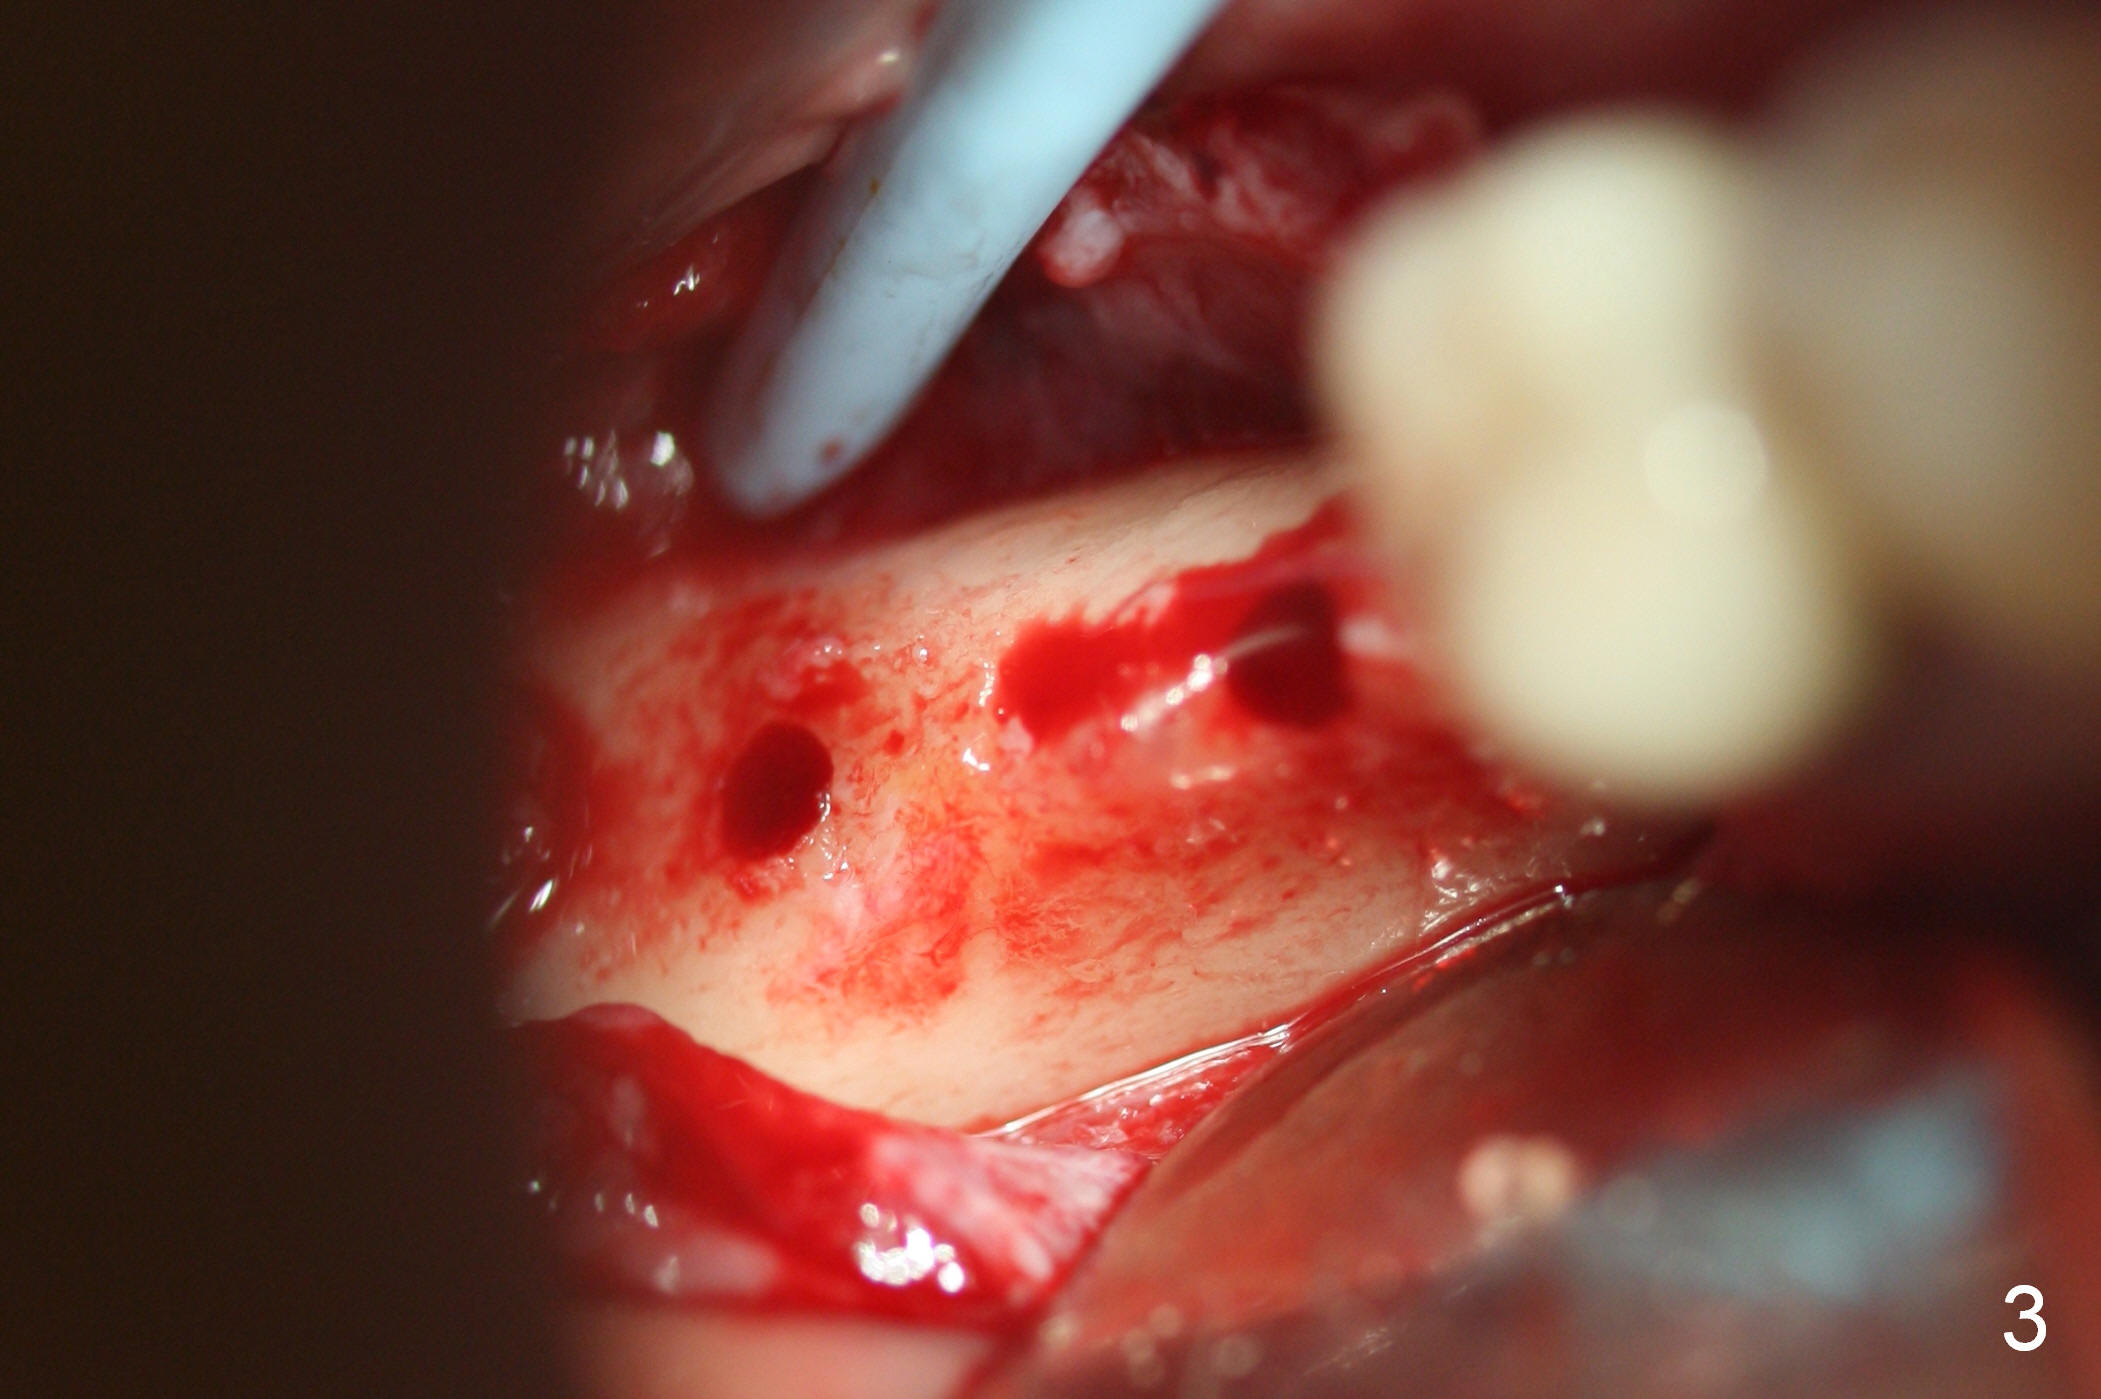

A preop photo shows different shape of pontics at #30 and 31 (Fig.1 <), suggesting different width of the edentulous ridge. Two of 8 mm parallel pins are inserted for position and trajectory (Fig.2 (red dashed line: the superior border of the Inferior Alveolar Canal). When they are removed from the osteotomy sites, the narrow ridge at #30 is shown (Fig.3). A 3x12 mm 1-piece implant is placed at #30, while a 4.5x10 mm 2-piece one at #31 (Fig.4,5). It appears that it is necessary to place an implant at #32, since the tooth #1 is present (Fig.5). The suggestion is rejected by the patient due to finance. After extraction of the tooth #32 and insertion of collagen plug, an immediate splinted provisional is fabricated to cover the #32 socket as well (Fig.6). The provisional is modified (to remove the portion that covers #32 socket) 3-4 weeks postop.